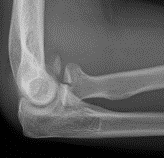

Dubberly Classification

| Type I | Type Ii | Type III |

|

Capitellar fracture

Capitellum + trochlea fracture In one piece Double arc sign seen on xray |

Capitellum + trochlea fractures In two separate pieces |

Double arc sign on xray |